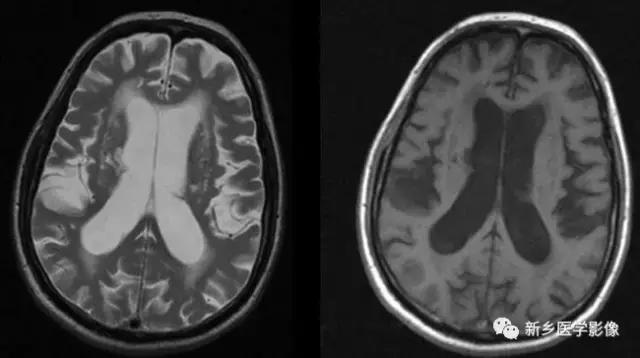

外伤后脑萎缩,感染后脑萎缩,脑梗死后脑萎缩CT可见扩大的脑室部分附近的脑实质呈片状低密度灶MR:T1WI呈低信号,T2WI呈高信号。同时脑沟及蛛网膜下腔增宽。

5.脑室周围白质软化症

主要与缺血缺氧及感染有关.常见于早产儿.是造成早产儿脑瘫的主要原因。由于脑室周围白质的血供分别来自脑室区和远脑室区的终动脉。未成熟儿终动脉深穿支的侧支循环尚未建立,而胚胎晚期脑室周围白质对缺血缺氧敏感。所以,脑室周围自质软化症多见于早产儿。由于病灶常为双侧性,故双侧侧脑室多同时扩大。脑白质内软化灶在CT扫描时表现为白质内斑片状低密度灶.MR T1加权图呈低信号,T2加权图呈高信号。

由于侧脑室周围有软化萎缩,故扩大的侧脑室外缘常不规则,不光整,这种不规则、不光整是本病引起脑室扩大的特征,另外,本病均表现有脑白质量减少及脑白质内斑片状软化病灶,脑白质减少严重时表现为部分区域白质消失,脑皮层与脑室侧缘接近甚至相连。CT表现为斑片状低密度灶。MR T1WI上呈低信号,T2WI呈高信号。